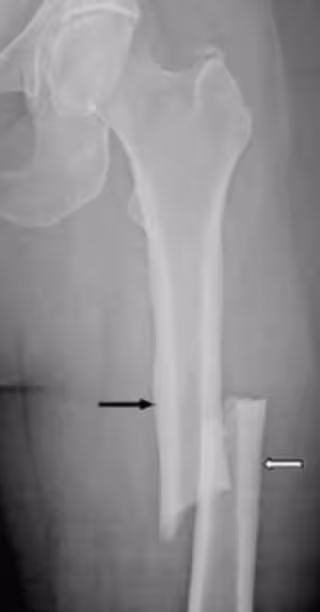

Fractura atípica de femur

Fractura atípica de femur - UB - Archivo